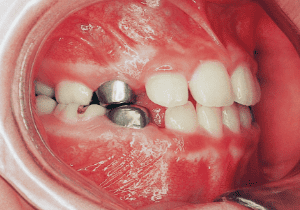

10 Perform lateral expansion of maxilla 7-4-’90 Midline is becoming deviated 9 years

11 During observation 4-1-’93 Midline deviation has become even greater 11 years 9 month

The Edgewise appliance was applied locally (8) and removed after 11 months (9). However, as the maxillary molar region gradually became crossbite, the maxillary arch was laterally expanded using a quad helix.

X-rays confirmed significant differences in the length and orientation of the mandibular ramus on the left and right sides. It was determined that orthodontic treatment alone would be insufficient, and a decision was made to proceed with treatment incorporating surgical intervention.